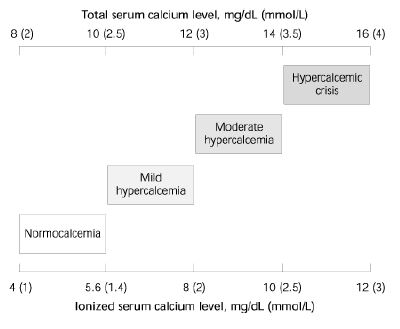

Hypercalcemia may be categorized based on total serum and ionized calcium levels (see Figure 1).

Figure 1: Spectrum of hypercalcemia5

Figure 1: Spectrum of hypercalcemia5